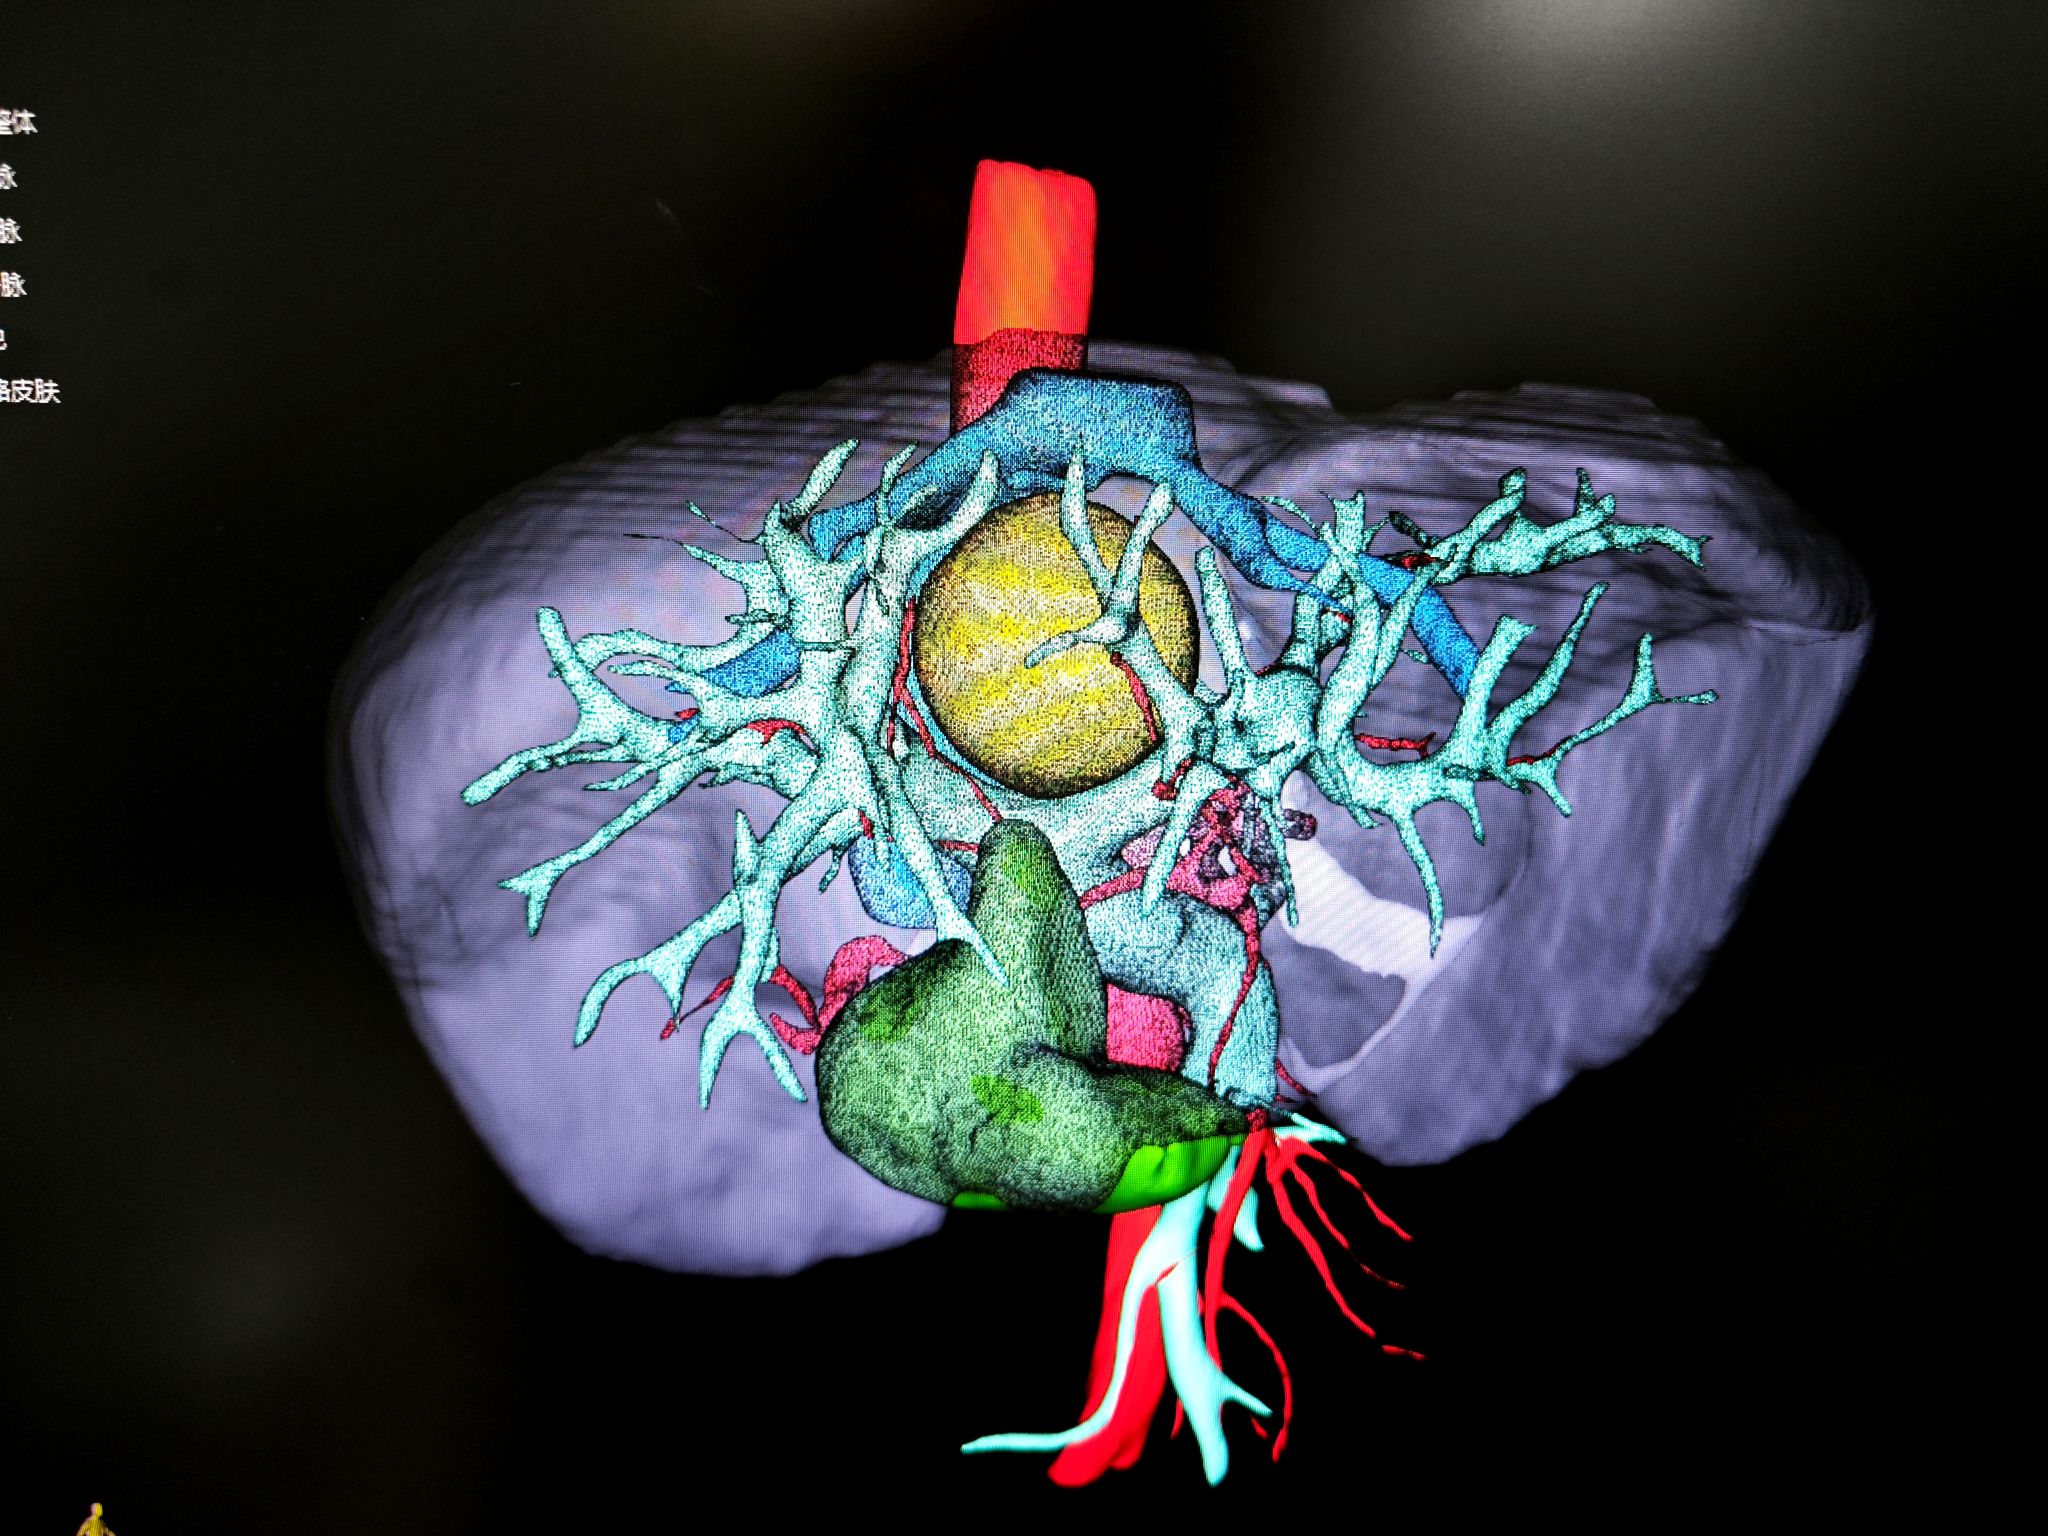

“必须把手术创伤降到最低!”团队达成共识。老年心血管内科率先行动,针对患者极高危高血压定制围术期血压管理方案;麻醉科吕建瑞教授团队设计了个体化血流动力学监测与保护策略;肝胆胰与肝移植外科王喆医师则借助三维肝脏重建技术,将肿瘤与血管的立体关系转化为“数字沙盘”。

屏幕上,血管的走向、肿瘤的边界清晰可辨。“肿瘤像一颗嵌在血管网中的‘定时炸弹’。”蒋安教授比喻道。肝胆胰及肝移植外科蒋安教授、曲凯教授、张威教授讨论后决定采用腹腔镜正中入路,劈开肝脏局部切除肿物,最大程度保留肝组织——如同在血管缝隙中“雕刻”肿瘤,既要完整切除病灶,又要保全肝中静脉、门静脉左右支及下腔静脉的完整性。

“没想到微创手术恢复这么快!”白先生感慨。特别值得一提的是,团队在术前特意用三维模型向他们讲解手术方案,“那些血管和肿瘤的立体图像,让我们真正理解了医生的良苦用心。”

4.人文温度:三维重建技术不仅用于手术规划,更成为医患沟通的桥梁,让医疗更具温度。